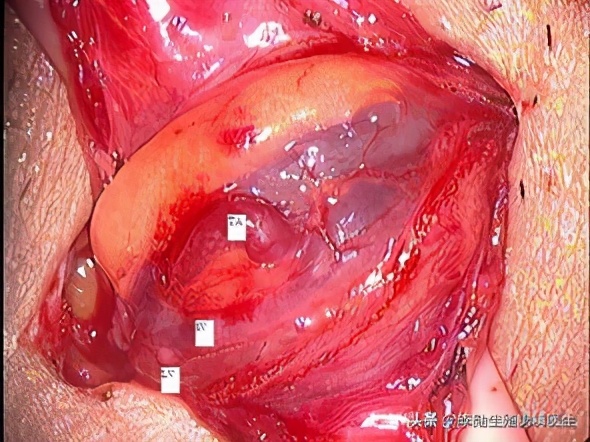

本人和助手正在做显微镜下低位精索静脉结扎手术